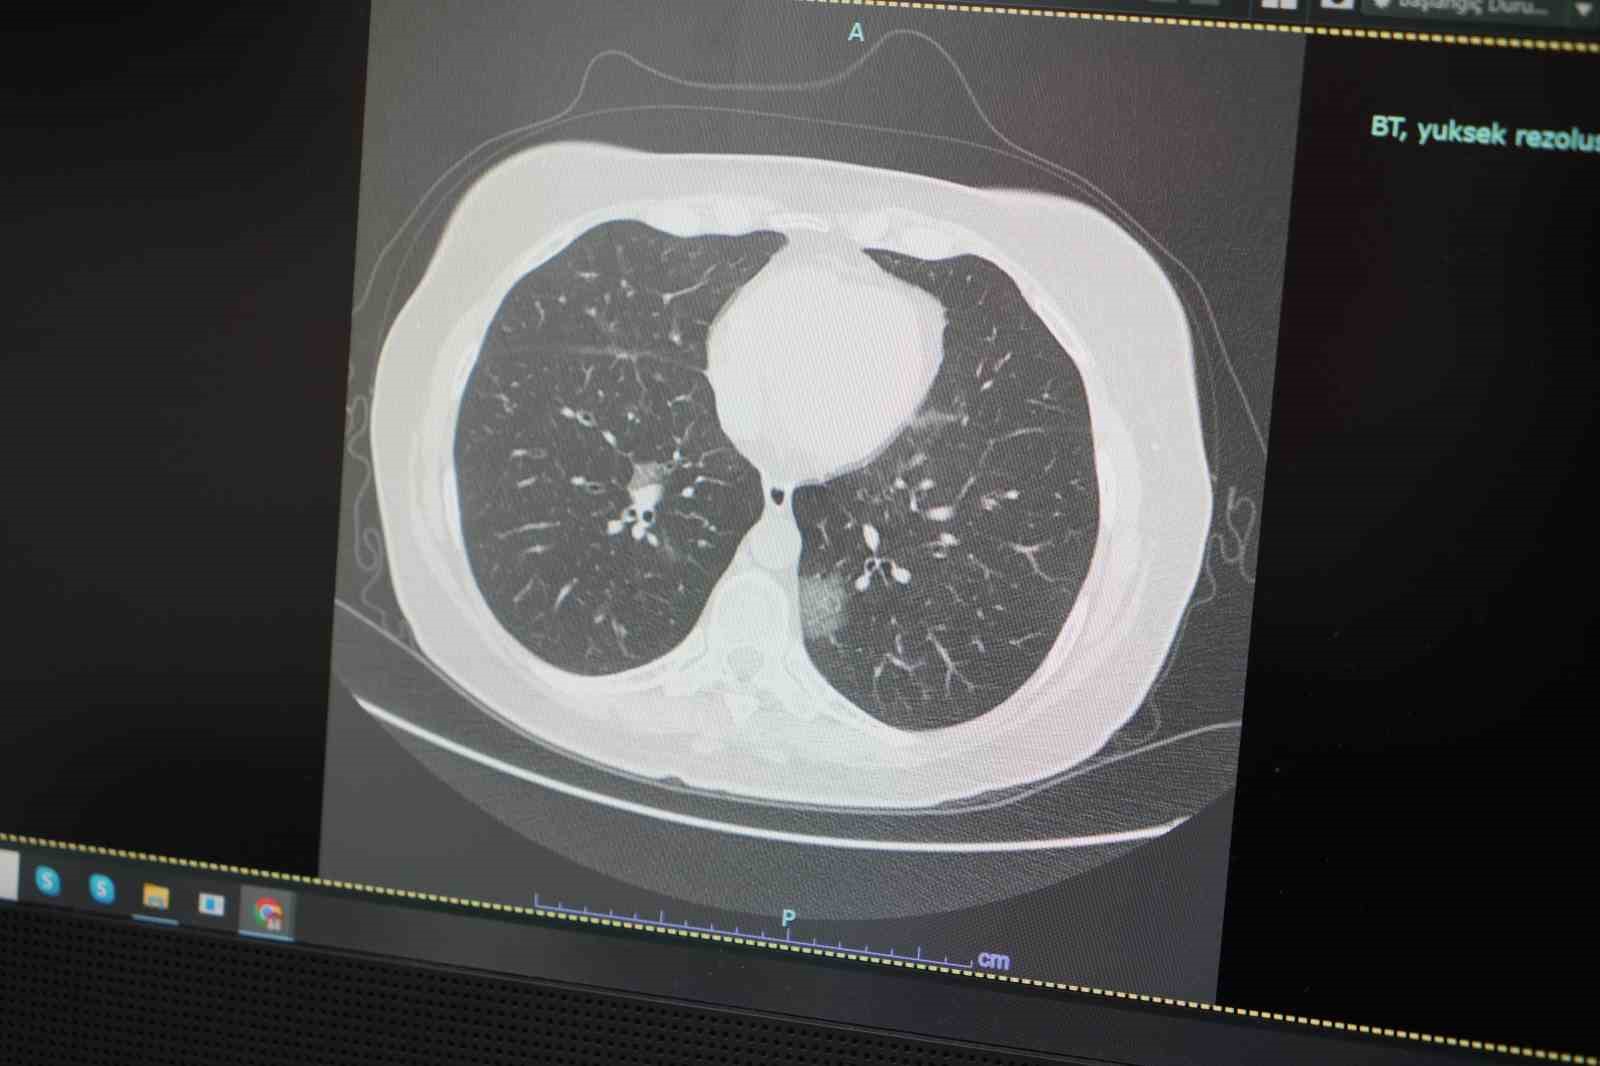

Mayıs ayıyla birlikte doğada yoğunlaşan polenlerin, alerjik bünyeye sahip kişilerde ciddi solunum yolu problemlerine yol açabileceğini ifade eden Prof. Dr. Özkaya, "Havaların ısınması ile birlikte insan hareketliliği artıyor. Bu da viral enfeksiyonların yayılımını hızlandırıyor. Aynı zamanda alerjenlerin de etkisiyle hastalarda nefes darlığı, öksürük, burun akıntısı gibi semptomlar görülüyor. Covid-19’un da benzer belirtiler göstermesi, tanı konulmasını zorlaştırabiliyor" dedi.

Hastalıklardaki belirti benzerliğine dikkat çeken Özkaya, "Alerjik rinit ve alerjik astım başta olmak üzere, havaların ısınması ile çiçek ve ağaç polenleri birden solunan havaya karışacak ve artmış, geçmeyen, uzun süren öksürük, burun ve boğaz rahatsızlıkları ile astım benzeri zatürre ve bronşit vakaları göreceğiz. Hastalarımız maalesef, geçmeyen, uzamış öksürük ve nefes darlığı şikâyetlerinin alerjik mi yoksa viral bir başka bir hastalık mı olduğunu anlayamıyor. Okulların açık olması ve ısınan hava ile özellikle çocuklarımız polen dolu bu dış ortamda daha fazla hareketli zaman geçirmeleri ve ani ısı değişikliklerinden çabuk etkilenmeleri nedeni ile hem alerjik şikayetlerinde hem de influenza, RSV, Adeno ve Covid virüsleri başta olmak üzere viral etkenlere daha fazla maruz kalacaklar. Bunun sonucu hem çocuklarımızda uzamış öksürük ve ateş şikayetleri olacak, hem de bu virüsleri evdeki büyüklere taşıyacaklar. Okullarda özellikle öğretmenlerimiz ve velilerimiz bu konuda uyanık olmalarını öneriyoruz. Ve artık mevsimlerin, iklimlerin birbirine karışması ile çevresel değişiklerden etkilenen hastalıklar da birbirine karışıyor. Öksürük, ateş ve nefes darlığı çeken ve düzelmesi geciken, iyileşmeyen her hastanın mutlaka göğüs hastalıkları uzmanına görünmeleri gerekiyor" şeklinde konuştu.